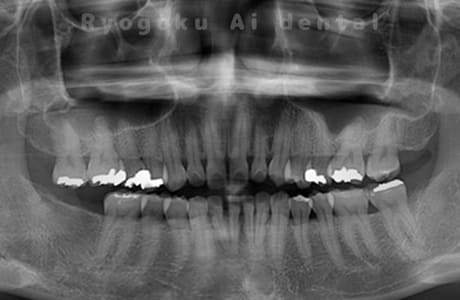

重度な歯周病を

改善する再生療法

最先端の歯科材料を用いて

歯周組織の再生

深い歯周ポケットに対して行う治療法で、衛生士による歯石取りでは十分に取りきることができなかった歯石を外科的に除去し、歯を支える失った骨を回復させる手術です。

かつては、深い歯周ポケットに対しては単にポケットを減らすことが主流でしたが、現在では再生のための薬(リグロス、エムドゲイン)や骨補填材の進化により元の健康な状態に戻すことが可能となってきました。

再生療法はそのような最先端の歯科材料を用いて組織の再生を促し、歯周組織を元の健康な状態に戻すための治療法となります。